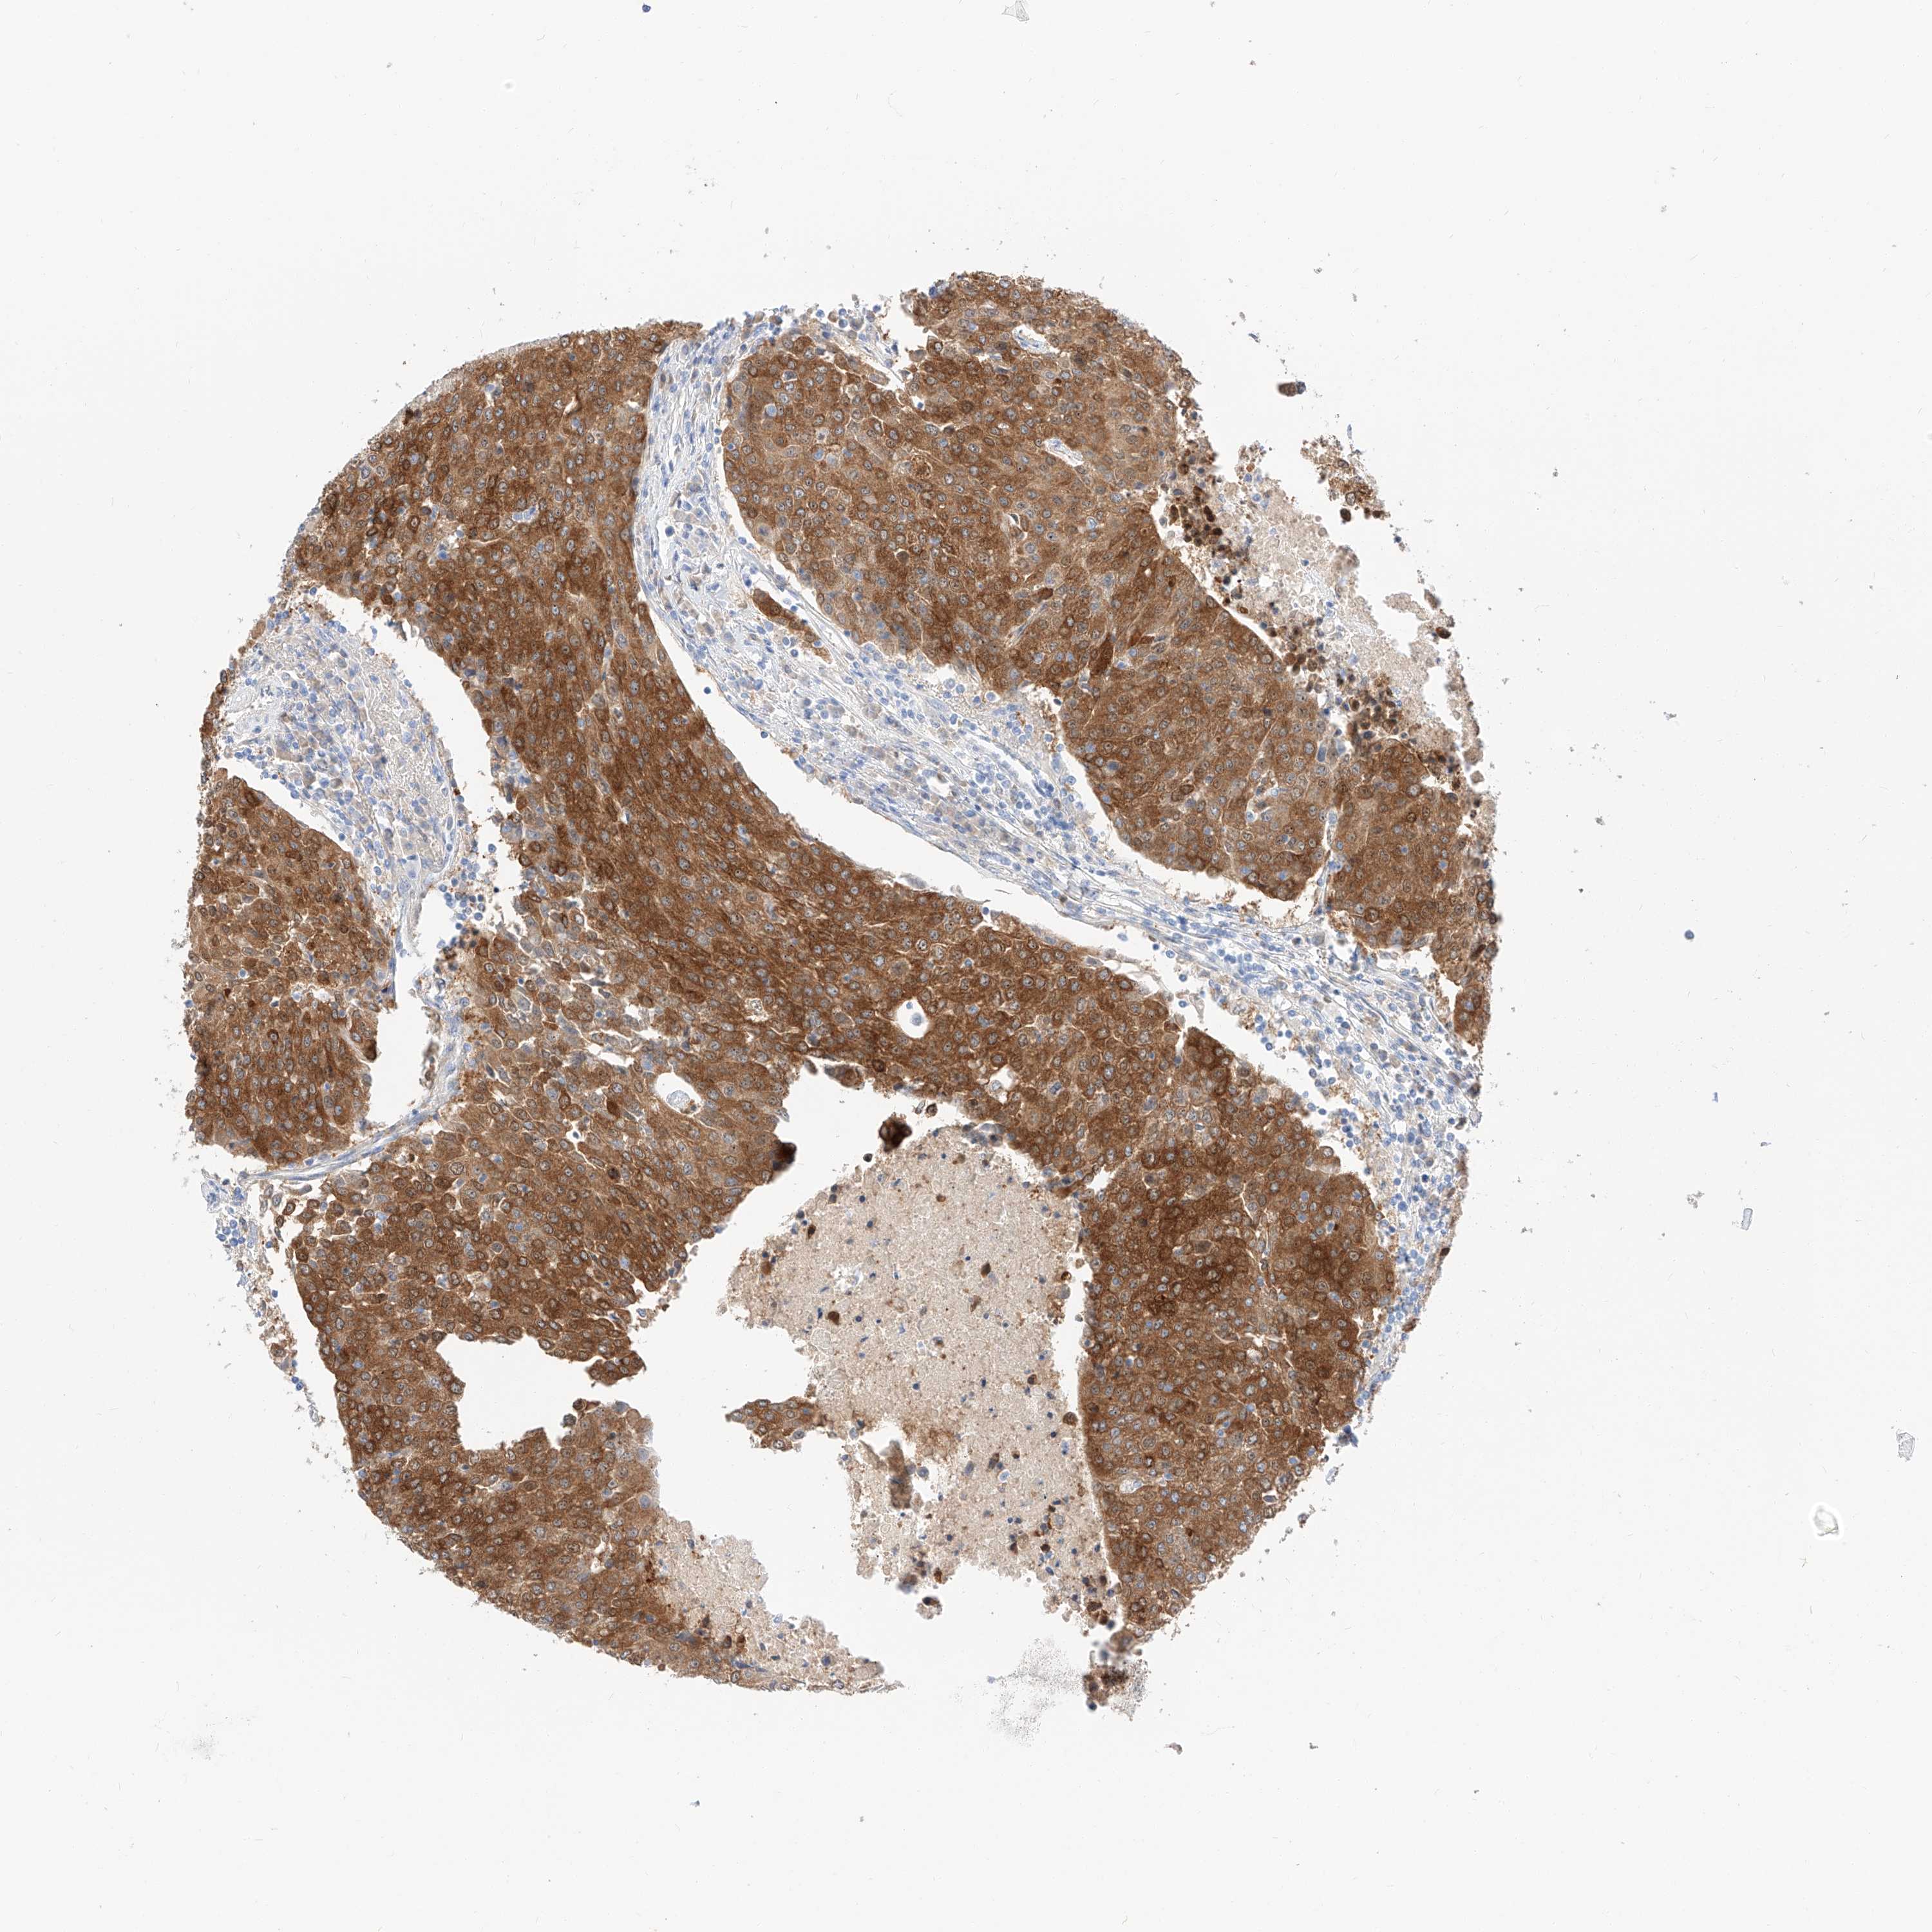

UROTHELIAL CANCER - Protein expressioni

A mouse-over function shows sample information and annotation data. Click on an image to view it in a full screen mode. Samples can be filtered based on level of antibody staining by selecting one or several of the following categories: high, medium, low and not detected. The assay and annotation is described here.

Note that samples used for immunohistochemistry by the Human Protein Atlas do not correspond to samples in the TCGA dataset.

Antibody stainingi

Antibody staining in the annotated cell types in the current human tissue is reported as not detected, low, medium, or high, based on conventional immunohistochemistry profiling in selected tissues. This score is based on the combination of the staining intensity and fraction of stained cells.

Each image is clickable and will lead to virtual microscopy that enables deeper exploration of all samples and also displays staining intensity scores, fraction scores and subcellular localization as well as patient and tissue information for each sample.

Antibody HPA029712

Antibody HPA029713

Staining

High

Medium

Low

Not detected

Intensity

Strong

Moderate

Weak

Negative

Quantity

>75%

75%-25%

<25%

None

Location

Nuclear

Cytoplasmic/membranous

Cytoplasmic/membranous,nuclear

Urothelial carcinoma, Low grade

Urothelial carcinoma, High grade